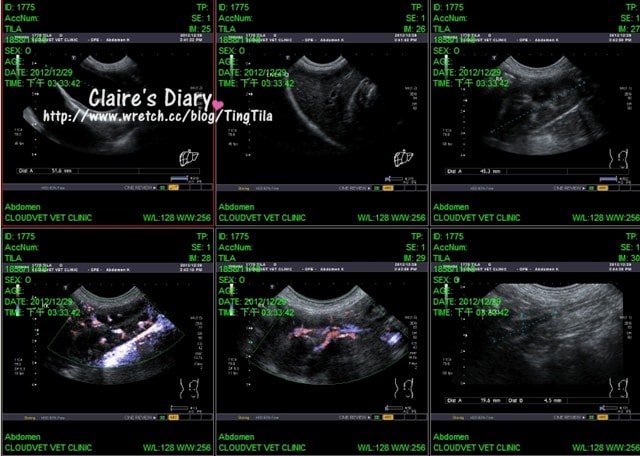

馬尾束症候群的部份,骨頭間的間隙不夠大,有點狹窄 ((主要看下排中間的照片))

比上次看起來再嚴重一點點了!有受到壓迫~X光看起來也比較不透光

椎間盤看起來也硬化的趨勢,硬化就會壓迫到神經

居家要做溫灸,如果發現TILA後腳沒有力氣就要注意回診!!

關於x光片,醫生有講解在X光片上每個器官的位置給我聽

我現在只記得正確的心臟與胃的位置

還看的到TILA的食物,還有便便的形狀~醫生說TILA的便便是一顆顆的很好

寬關節的部分看起來還蠻圓滑的,算漂亮?!哈~((真的這樣說唷

雖然有一點點鬆,但還可以接受

氣管的部份看起來也很好~沒問題